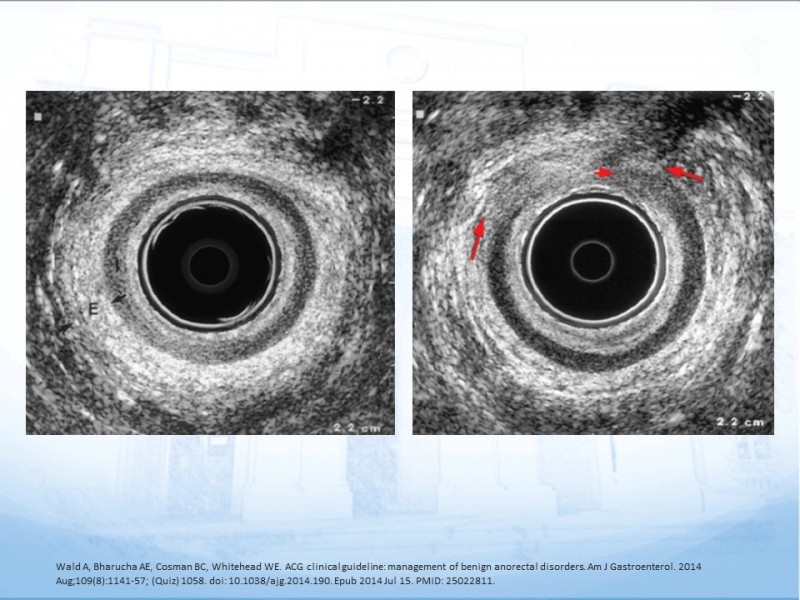

Incontinencia Fecal